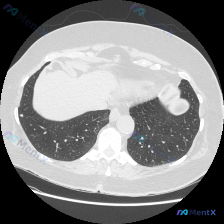

看到一份胸部CT肺窗横断面的病例资料,整理了一下分析思路,大家看看有没有补充的。 病例信息: - 图像层面:胸部较低层面,显示双肺下叶、部分心脏、肝脏及腹部结构 - 右肺下叶病灶:靠近肺门区域的实性病灶,形态不规则,边界清晰,周边有支气管血管束向病灶汇聚 - 病灶内部:可见支气管充气征,支气管有扩张...